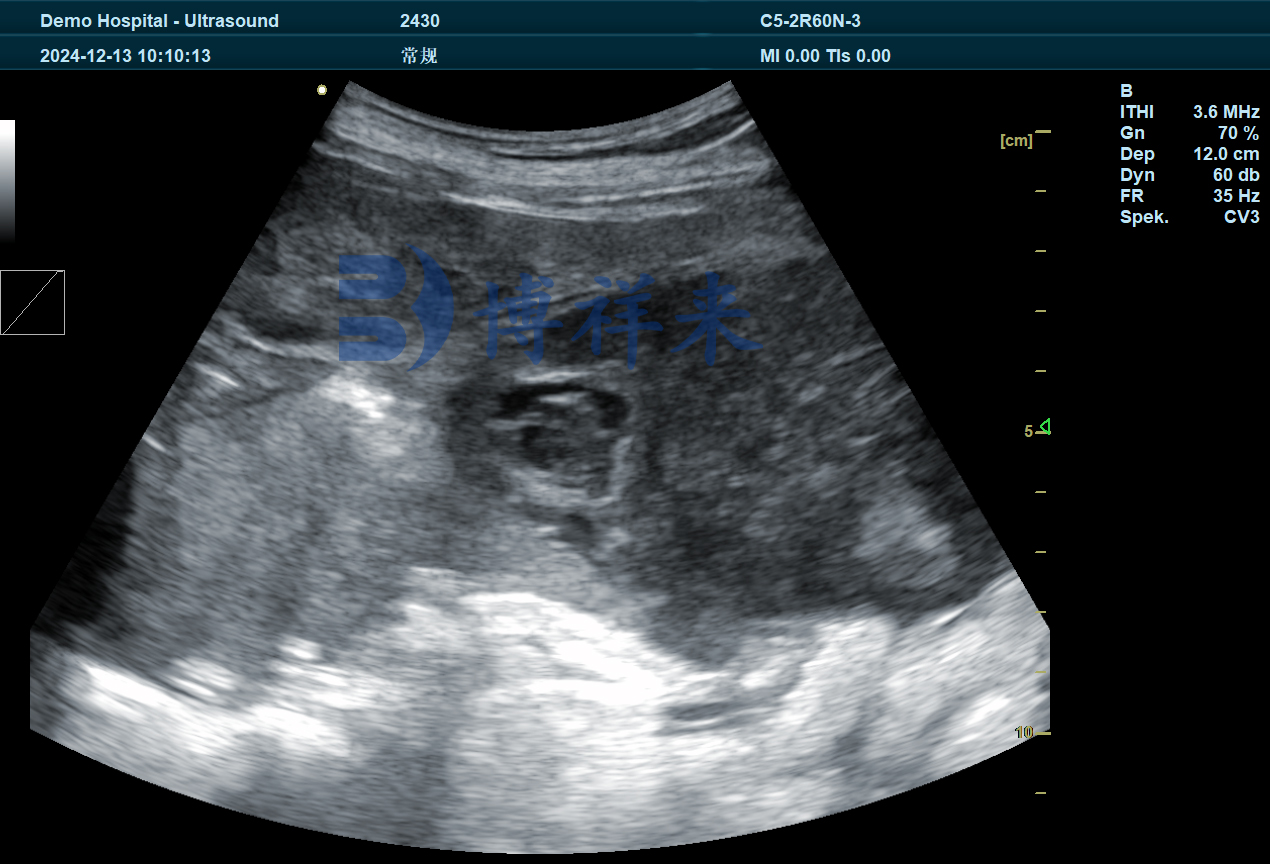

卵泡B超图像特征识别

在B超图像中,卵泡呈现为多个边缘清晰、黑色圆形结构,大小通常在0.5-1.2cm之间。通过连续监测,可以判断卵泡是否处于:

生长期(小且数量多)

成熟期(逐渐增大,接近排卵)

排卵期(卵泡数量减少、部分塌陷)